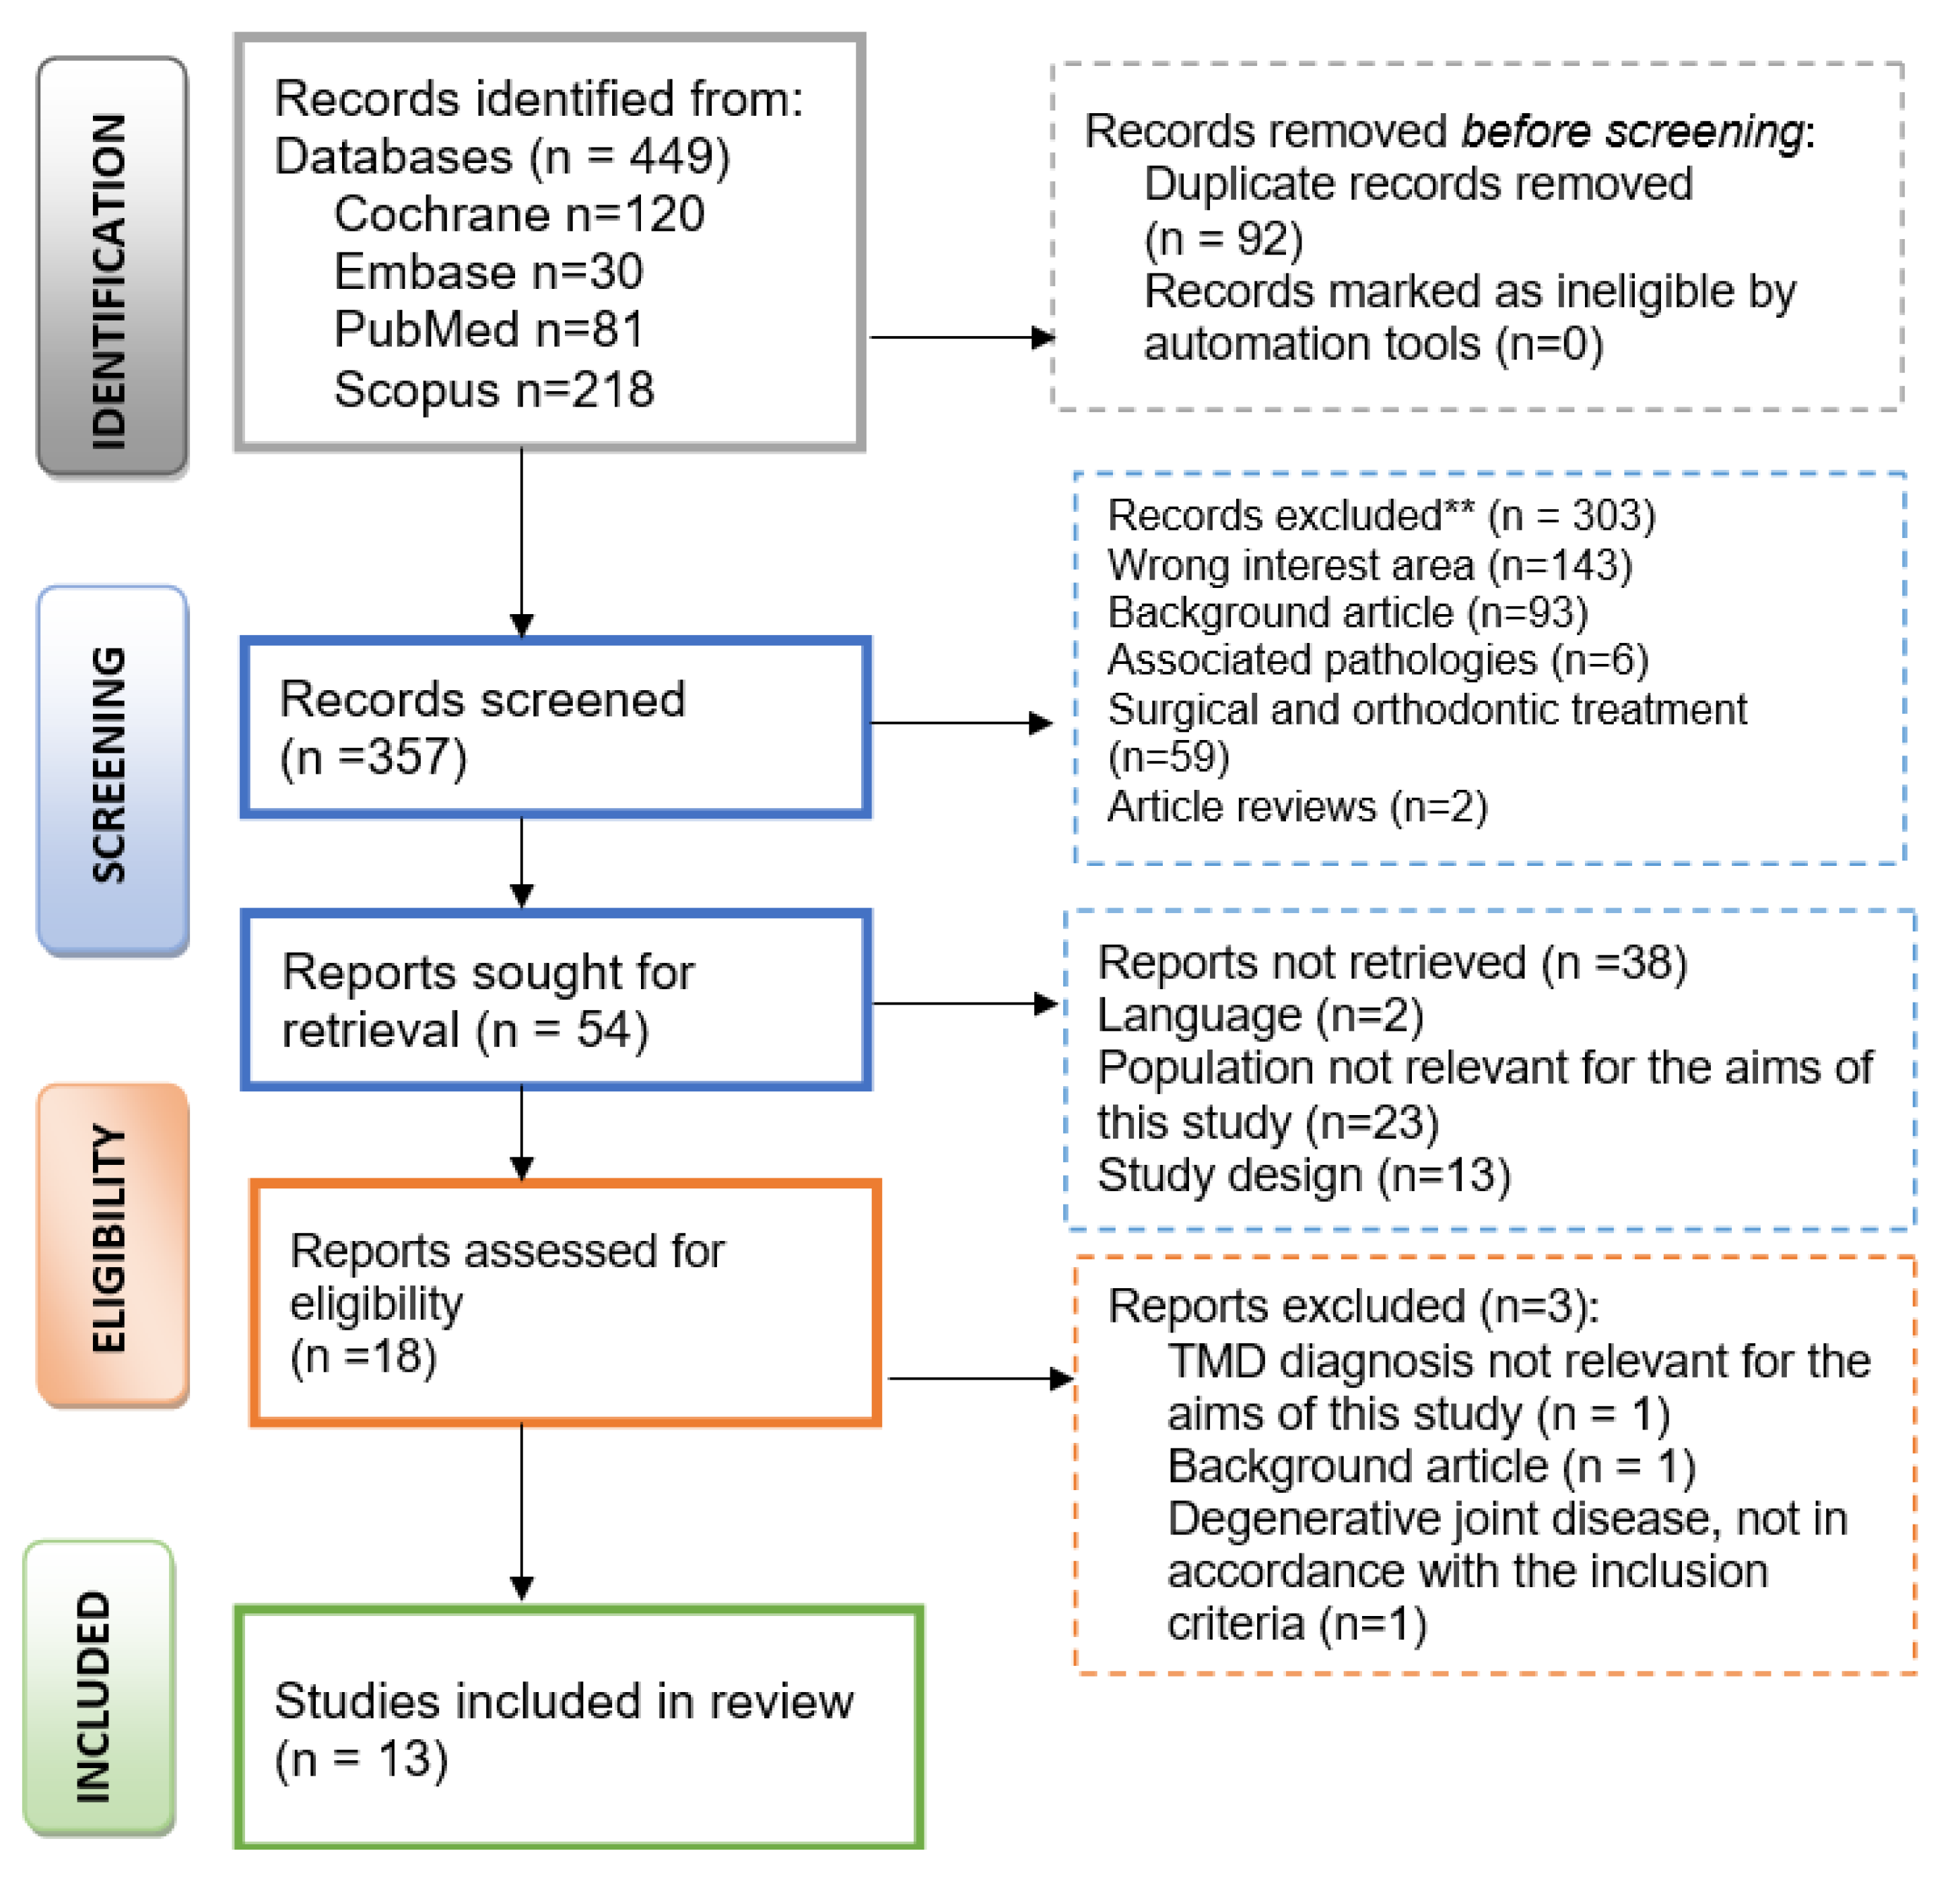

2. Materials and Methods

3. Results

3.1. Data Collection